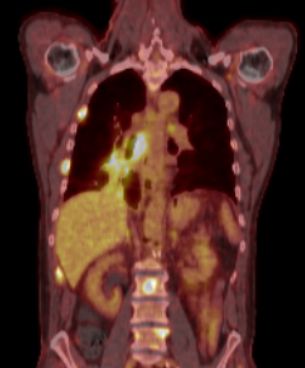

blauer Punkt 57-jähriger Mann mit einem 5cm großen Plattenepithelkarzinom des rechten Lungenoberlappens. 3/20 entfernten Lymohknoten waren positiv. Eine paratracheale Metastase stellt sich nicht dar. 4 Wochen nach Operation trat eine Hautmetastase praesaral auf.